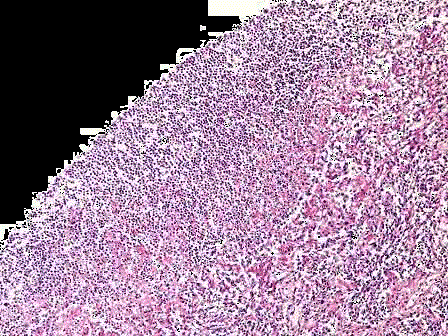

问题 患者,男,45岁。因高热、咳嗽、咳大量脓痰入院。X线示一有液平面的空腔。手术切除病变肺组织,巨检见病变中央呈囊腔状,腔内含黄色脓液,镜下腔壁可见大量变性坏死中性粒细胞,如图所示,可诊断为 ( )

选项 A.肺结核 B.肺脓肿 C.小叶性肺炎 D.大叶性肺炎 E.肺癌

答案 B